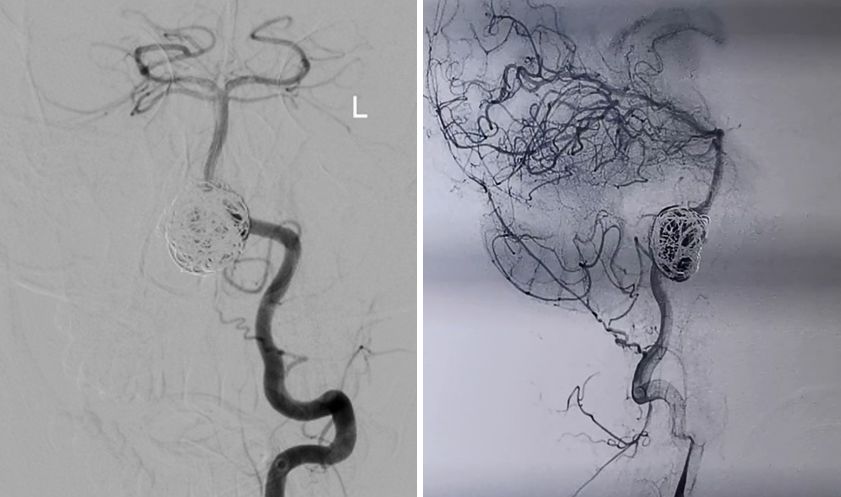

左椎动脉造影显示椎-基底动脉及远端血管通畅,动脉瘤虽然部分显影,但是PED最终会让动脉瘤完全修复。

结局:

患者术后各项体征稳定,无特殊不适。两天后出院。